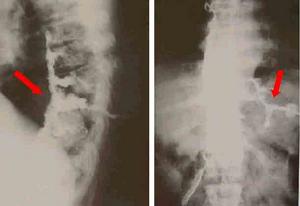

遺傳性痙攣性截癱HSP的診斷主要基於臨床症狀體徵,陽性家族史,並排除其他疾病。因此,HSP的鑑別診斷很重要,特別是對臨床特徵不典型及沒有相同疾病家族史的患者。目前,基因診斷已成為可能,但只限於已克隆的5型疾病基因的突變檢測。肌活檢有助於HSP-7型的診斷頸椎病常有上肢受累,神經根性疼痛,頸椎X線片及MRI示頸椎骨質增生。多發性硬化有緩解與復發的病史,視神經炎,MRI示腦部脫髓鞘改變。肌萎縮側索硬化有上肢肌萎縮,肌束震顫,肌電圖示巨大電位改變。Arnold-chiari畸形有共濟失調錶現,頭顱MRI可確診。脊髓小腦型共濟失調以共濟失調錶現為主,眼球運動障礙,構音障礙等。本病須與Arnold-Chiari畸形、頸椎病,多發性硬化、腦性癱瘓和遺傳運動神經元病等鑑別。

3、MRI頭顱MRI一般無異常,但某些病例可表現胼胝體發育不良,大腦、小腦萎縮。頸段或胸段脊髓MRI可顯示脊髓萎縮。